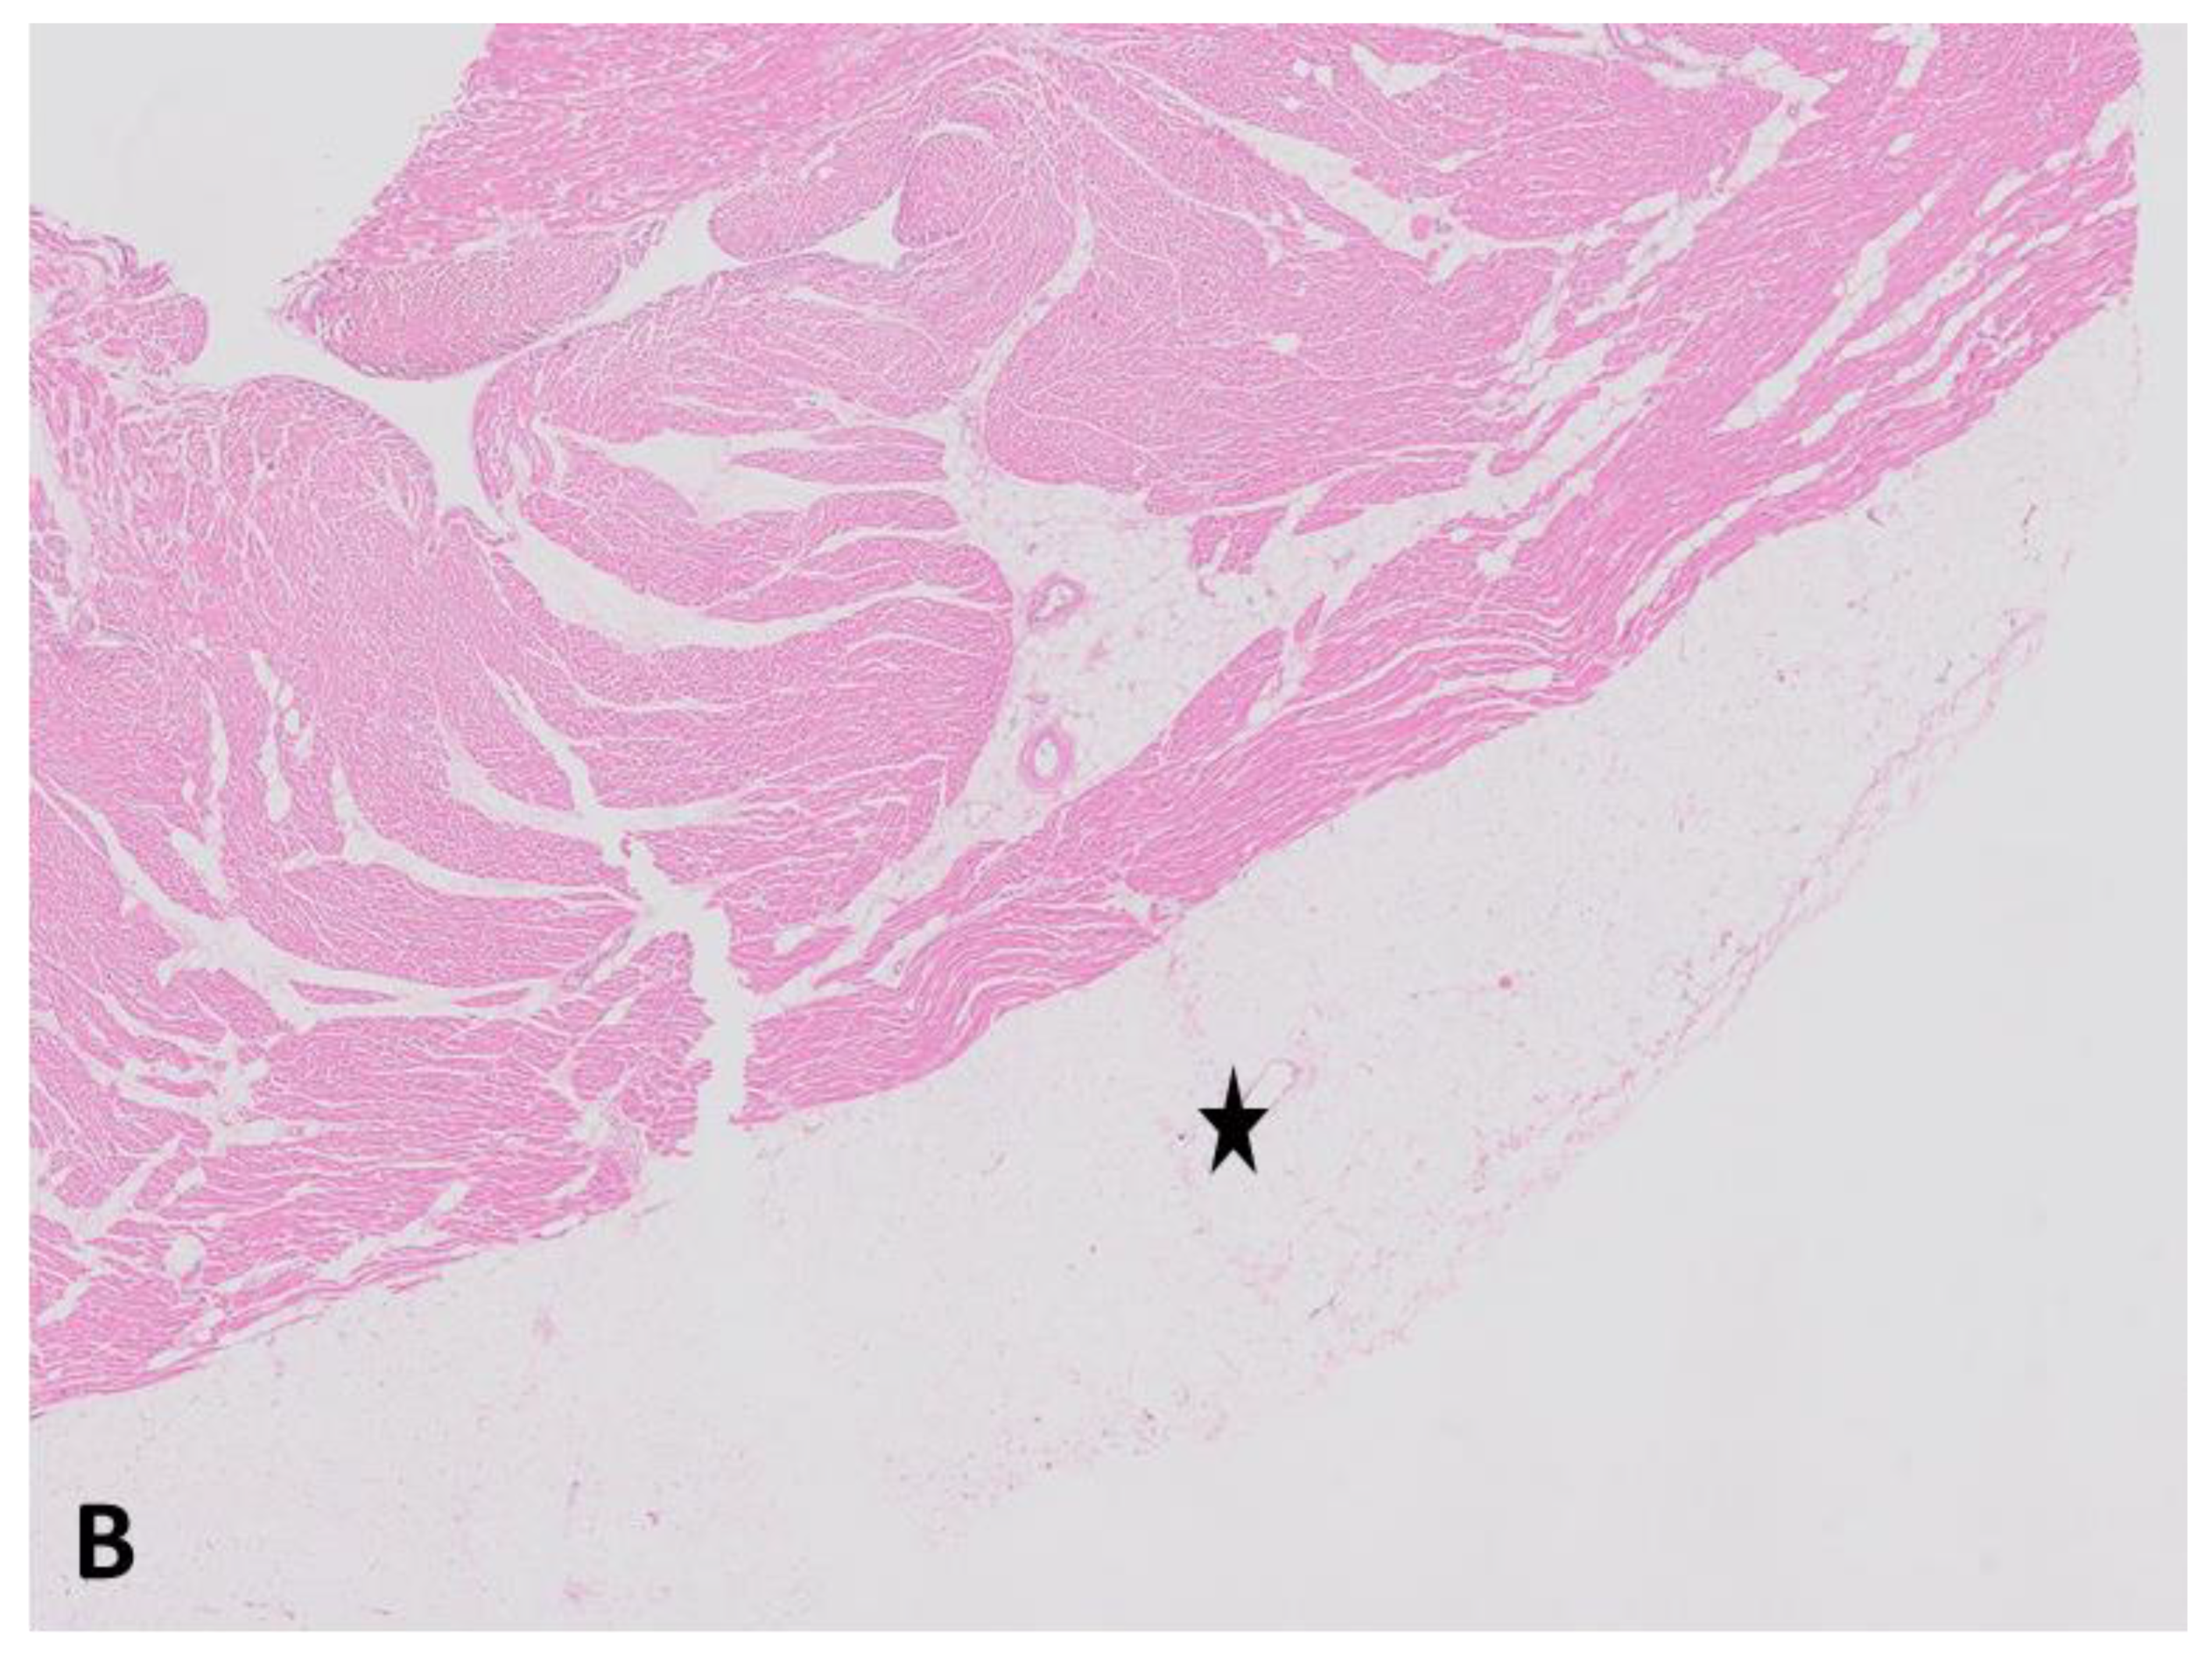

Case 2. A previously healthy 33 years old male presented with out-of-hospital cardiac arrest due to persistent ventricular fibrillation. Resuscitation was unsuccessful. Health and family history of the mother were uneventful. The biological father of the patient was unknown. On autopsy, extensive fatty and fibrotic changes of the myocardium of the left ventricle were observed (Figure 2A,B).

Figure 2.

Hematoxylin- and Eosin-stained sections of the left ventricle of the heart (A) with extensive fatty and fibrotic changes of the myocardium and the right ventricle of the heart and (B) with only epicardial fat. Asterisk indicates fatty tissue. Arrows indicate fibrosis.